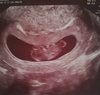

U mnie dzidzia dzisiaj wg om 9+4, 27 mm to wg usg 9+3, słyszałam serduszko, po krwiaku nie ma śladu, a tu moja fasolinka :)

IMG_20180831_182630.jpg